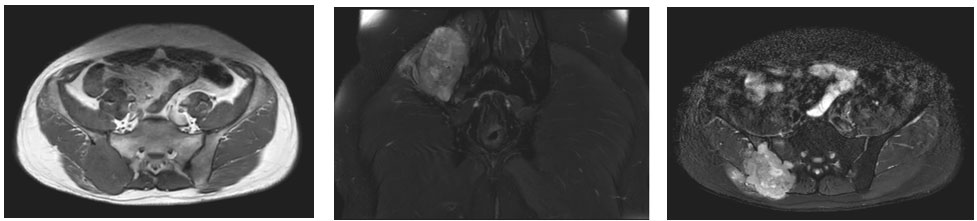

Ameliyat öncesi: MR’da aynı lokalizasyonda düzensiz sınırlı, yumuşak dokuya uzanım gösteren tümör dokusu görülmekte